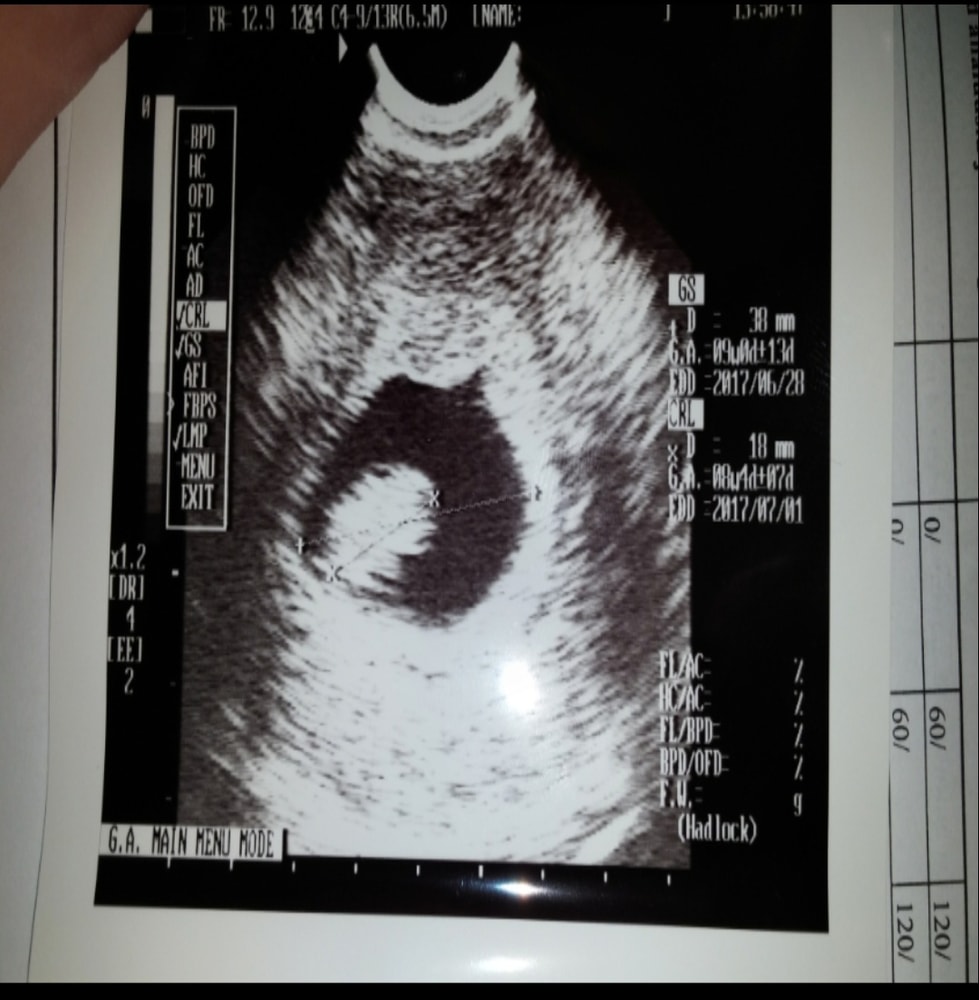

А это сын